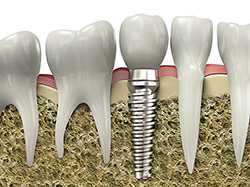

implantsIf you have missing teeth, it is crucial to replace them. Without all your teeth, chewing and eating can destabilize your bite and cause you discomfort. When teeth are missing, your mouth can shift and even cause your face to look older. Implants are a great way to replace your missing teeth, and if properly maintained, can last a lifetime!

An implant is a new tooth made of metal and porcelain that looks just like your natural tooth. It’s composed of two main parts: One part is the titanium implant body that takes the place of the missing root, and the second part is the tooth-colored crown that is cemented on top of the implant. With implant treatment, you can smile confidently knowing no one will ever suspect you have a replacement tooth.

In addition to tooth replacement, implants may be used to anchor dentures, especially lower dentures that tend to shift when you talk or chew. For patients with removable partial dentures, implants can replace missing teeth so you have a more natural-looking smile.